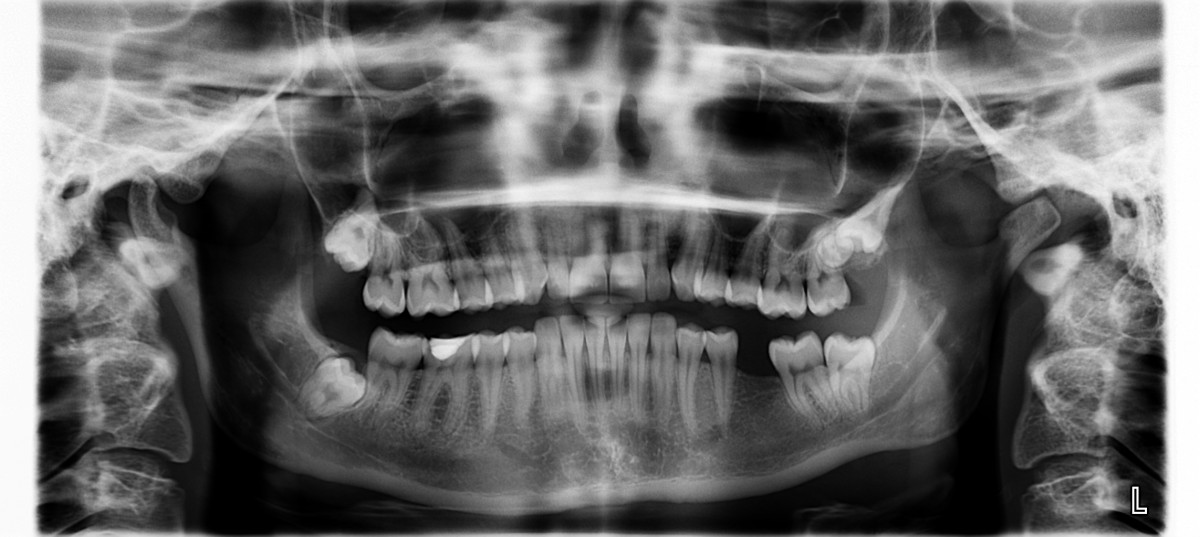

Röntgensäteily lääketieteessä

- Röntgensäteilyä käytetään lääketieteen kuvausmenetelmänä

- Perustuu eri aineiden kykyyn absorboida röntgensäteilyä (vuorovaikutus aineen elektronien kanssa)

- Säteily läpäisee paremmin kudosta kuin luuta (luu koostuu raskaammista alkuaineista kuin pehmytkudos)

Kuvat: Pxhere / CC0